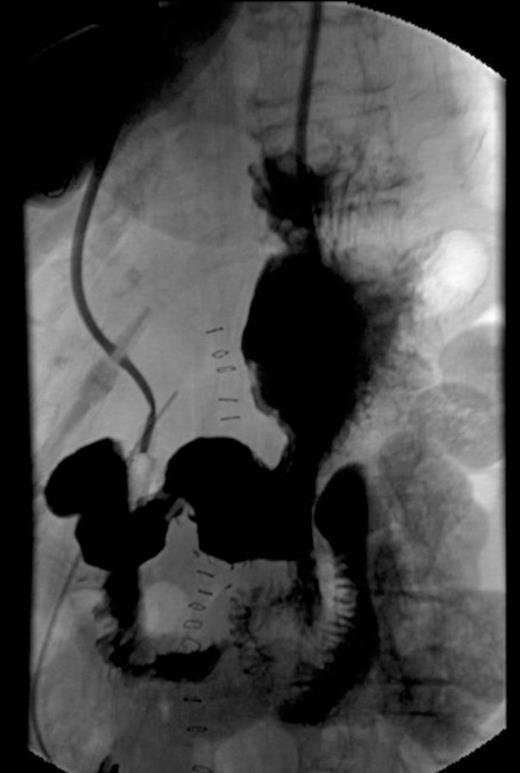

Post-operative UGI series showing no anastomotic leaks and patency of anastomosis.

The patient had an uneventful postoperative course. Initially, her nasogastric tube was kept in place and her parenteral nutrition was maintained. There were no clinical or biochemical signs of a pancreatic leak. A postoperative upper GI series was done on day 6 and the anastomosis was in-tact (Fig. 2). There were no leaks. After the contrast study, her suction drain was removed. At day 7, the patient was tolerating a transitional diet. By day 9, she was tolerating a full diet and discharged home. At her six month followup, the patient was doing well with no complaints. Oncology suggested no chemotherapy at the time.